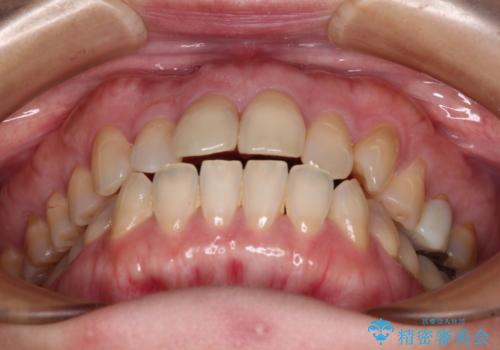

- 前歯のデコボコと口元の突出感を気にして来院された患者様です。

上下前歯がくちばしのように突出していたため、上下左右の第一小臼歯4本を抜歯し、ワイヤー装置にて矯正治療を行うこととしました。

上顎骨に対して下顎骨がやや前方位に位置しているため、歯肉退縮を回避するために下顎前歯をあまり内側に移動させることができない状況でしたが、十分に口元の突出感を改善することができました。